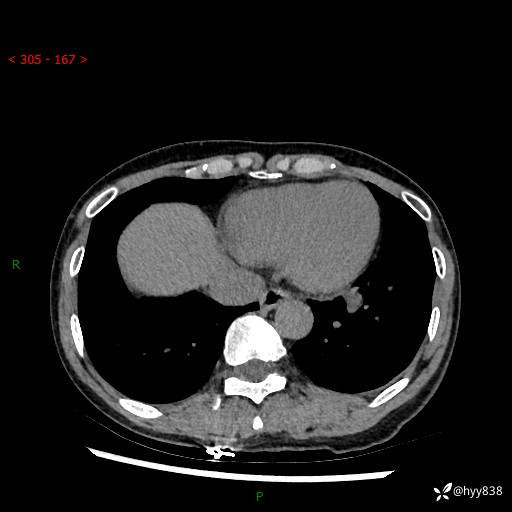

【患者信息】:55岁/女

【主诉】:咳嗽咳痰半月,发现肺占位2天

【现病史及既往史】:患者半月前出现咳嗽咳痰,伴头晕胸闷、无发热气喘。于当地医院住院行抗感染治疗1周(具体药物不详),后咳嗽减轻,但仍未完全缓解,复查胸部CT示:左肺下叶1.8*1.2结节软组织影。为求进一步诊治来我院,门诊以“肺占位”收入院。 自患病以来,精神、饮食、睡眠尚可,大小便正常,体力体重无明显减少。

【检查】:胸部CT平扫+增强

各期CT值:40hu 57hu 49hu